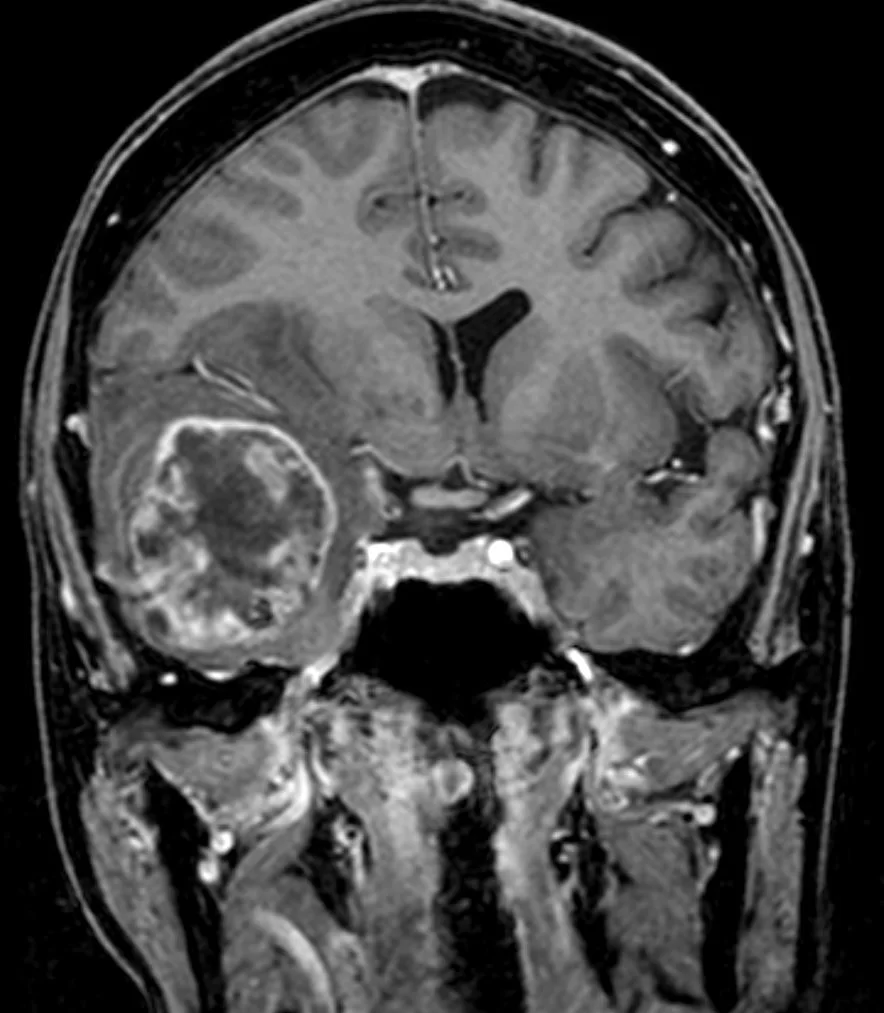

Η μαγνητική τομογραφία ανέδειξε ευμεγέθη χωροκατακτητική εξεργασία δεξιά κροταφικά με σημαντικό περιεστιακό οίδημα, ύποπτη για κακόηθες γλοίωμα.

Διενεργήθη δεξιά κροταφική κρανιοτομία και πλήρης εξαίρεση της βλάβης με τη βοήθεια νευροπλοήγησης, διεγχειρητικού υπερήχου αλλά κυρίως με τη χρήση 5-ALA ανοσοφθορισμού.

Η μετεγχειρητική μαγνητική τομογραφία εγκεφάλου (substraction sequences) δείχνει πλήρη αφαίρεση της βλάβης. Η ιστολογική εξέταση ανέδειξε γλοιοβλάστωμα (IDH1/2 mutant, MGMT neg).